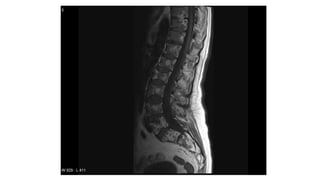

MRI isthe most accurate technique forshowing the

extension into both the medullary cavity and the soft

tissues can be accurately defined, as can the

relationship to important nerves and blood vessels.

MRI provides this information better than CT